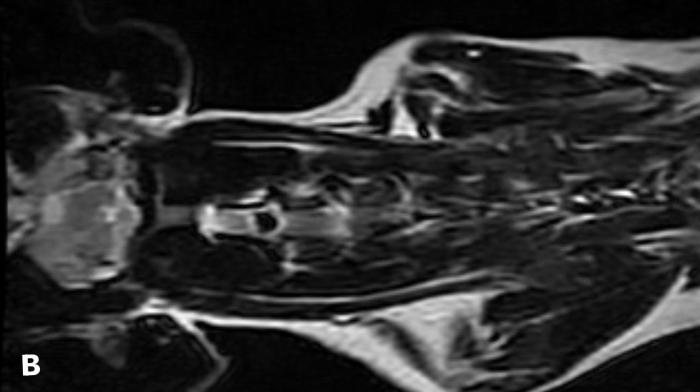

Se procedió a realizar un slot ventral a nivel C2-C3 (Figura 2). El procedimiento transcurrió sin incidentes relevantes. La presión arterial media se mantuvo dentro de un rango aceptable, con valores entre 70 y 85 mmHg, sin descensos inferiores a 65 mmHg. La capnografía y la saturación de oxígeno se mantuvieron sin alteraciones significativas. Se registró una leve bradicardia durante el abordaje quirúrgico, sin repercusión hemodinámica.

Figura 2. Vista de slot ventral C2-C3.